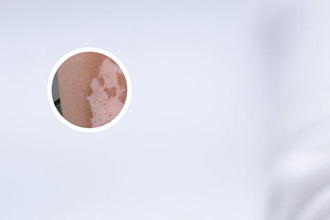

伍德燈皮膚下是灰白色,很可能是白癜風(fēng),但需要結(jié)合其他檢查結(jié)果,才能確診!伍德燈是一種皮膚檢查工具,它利用紫外線照射皮膚,觀察皮膚的熒光反應(yīng),來幫助醫(yī)生診斷皮膚病。白癜風(fēng)患者在伍德燈照射下,白斑會呈現(xiàn)明亮的藍(lán)白色熒光,這在醫(yī)學(xué)上被稱為“伍德燈陽性”。但這并不意味著所有伍德燈陽性的患者都是白癜風(fēng),還需要結(jié)合臨床癥狀、病史等進(jìn)行綜合判斷。很多皮膚病在伍德燈下也會呈現(xiàn)陽性反應(yīng),如無色素痣、花斑糠疹、頭癬、馬拉色菌性毛囊炎等。

白癜風(fēng)是一種色素性皮膚病,患者的皮膚上會出現(xiàn)大小不等、形狀不一的白色斑塊。白斑通常呈乳白色、瓷白色、淡白色或云白色,邊界清晰,表面光滑,與周圍正常皮膚界限分明。白斑可發(fā)生在身體任何部位,但較常見于面部、頸部、手背、四肢等暴露部位。白癜風(fēng)的病因目前尚不明確,可能與遺傳因素、自身免疫因素、神經(jīng)因素、精神因素等有關(guān)。